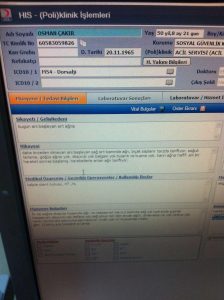

- FSM yakınındaki hastaneye bakıyorsun, Röntgen sonuçlarında çatlak bile yok. Kolaylıkla Rabia işareti yapabilir, kendini parmaklayabilir.

- Hastane kayıtlarına göre de, doktor “eline verdim yolladım” diyor. Ama adam nasıl olduysa 15 Temmuz soytarılığında Gazi oluvermiş.